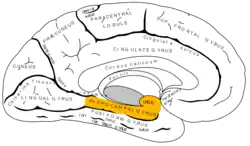

Medial view of left cerebral hemisphere. Parahippocampal gyrus shown in orange. | |

Medial surface of left cerebral hemisphere. Parahippocampal gyrus shown in orange.

Medial surface of left cerebral hemisphere. Parahippocampal gyrus shown in orange. -